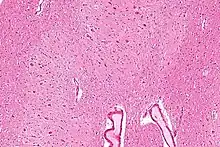

The dentate nucleus is highly convoluted, with gyri (ridges on the cerebral cortex) and sulci (furrows or grooves on the cerebral cortex). Its formation is coincident with a critical period of extensive growth in the fetal dentate. The dentate nucleus becomes visible in the cerebellar white matter as early as 11–12 weeks of gestation, containing only smooth lateral (towards the side(s) or away from the midline) and medial (towards the midline) surfaces. During this time, the neurons of the dentate nucleus are similar in shape and form, being mainly bipolar cells.[2]

During 22–28 weeks of gestation, which is the critical period in fetal development of the dentate nucleus, gyral formation occurs extensively over the entire surface.[3] Here, neurons mature into various forms of multipolar cells,[3] and the most frequent neuronal types are medium-sized to large neurons.[2]

Morphology

The dentate nucleus is highly convoluted[3] and can be divided into dorsal (motor) and ventral (nonmotor) domains. The ventral half is much more developed in humans than in great apes, and it appears to play an important role in fiber connection. Further, the ventral domain mediates higher cerebellar functions, such as language and cognition, as well as versatile and coordinated finger movement.[8] While it is generally accepted that the ventral region is more recent on an evolutionary timescale, current 3-Dimensional imaging raises questions regarding this assumption, as a third axis, the rostrocaudal axis, can now be analyzed.[3] In addition, current images show that the ventral region is not physically larger than the dorsal region in humans, as would be predicted if size increases with cognitive function.[1]